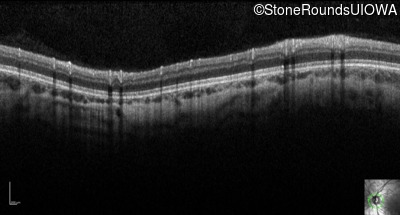

Optical Coherence Tomography - Right - 10/160 sc

Exemplar

Optical Coherence Tomography - Left - 10/200 sc

Exemplar / OCT Stack